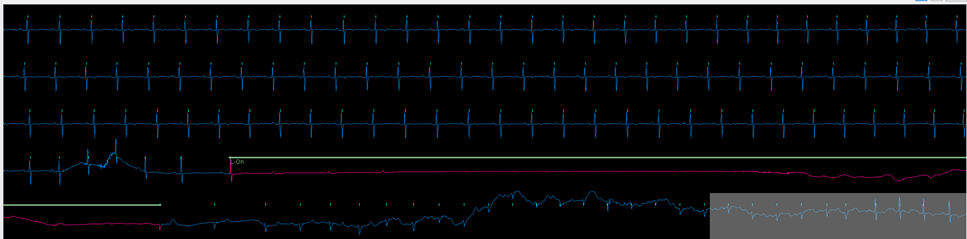

Instead, patients are being fitted with an AI-enabled monitor called ‘Zio XT’ which has been developed by digital healthcare company, iRhythm Technologies.

After up to 14 days of wearing the device, which is discreet and showerproof, the patient simply returns it by post for analysis by iRhythm using artificial intelligence (AI).

Using both AI and iRhythm’s team of certified cardiac physiologists allows weeks of data to be analysed in minutes and has proven to be very accurate in helping to diagnose a range of arrhythmias. It means patients can be treated faster without the burden of repeat testing, reducing pressure on hospital resources in the process.

Patient X was fitted with a Zio XT monitor as part of the NHS AI in Health and Care Award. During the wear time, the AI algorithm detected a 28 second period in which the patient’s heart had stopped beating while sleeping. This is known as ventricular asystole and can be life threatening if left untreated.

Zio’s AI technology detected the issue. The data was reviewed by one of the team’s highly specialised Physiologists and the patient’s physician was notified of the problem. Patient X was brought into hospital where he was fitted with a pacemaker and the condition was treated effectively.

Traditionally patients are monitored for a 24 - 48 hour period. Patient X’s heart stopped beating on day 10 of recording. Without iRhythm’s unique ability to monitor a patient for up to 14 uninterrupted days, patient X’s condition would have remained undiagnosed and untreated. This is therefore an example of how iRhythm and the NHS AI in Health and Care Award have literally helped save a patient’s life.